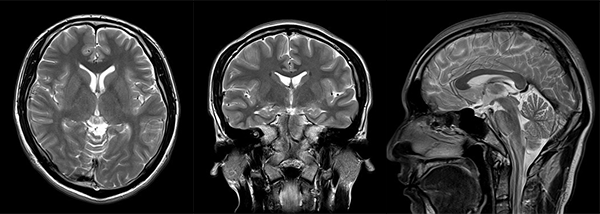

・体位を変えることなしに、任意方向(横断面だけでなく、縦や斜めなど)の断層面の撮像ができます。

頭部の断面像 いろいろな方向から撮影